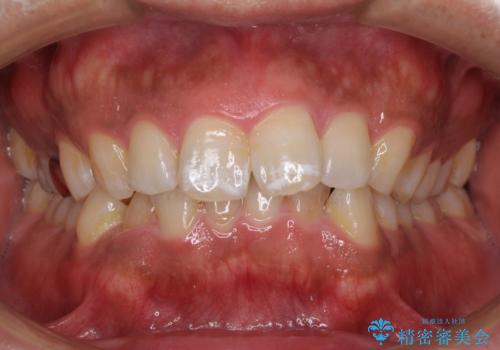

- 上下前歯部の叢生を気にして来院された患者様です。

レントゲン撮影により、右上奥歯が折れていることが分かりました。

患者様自身も何となく違和感を覚えていたとのことで、インプラント補綴治療を行うこととしました。

歯列不正は比較的軽微であったので、インビザラインによる矯正治療とし、矯正治療中にタイミングを見て抜歯とインプラント埋入を行う予定としました。